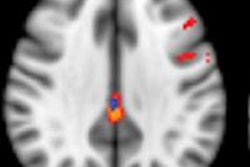

The marker most commonly used is PET imaging of brain metabolism, using FDG as a tracer. This technique shows typical hypometabolic patterns in different dementia syndromes, with an overall superior sensitivity compared with hypoperfusion assessment by SPECT. A second molecular marker used for the differential diagnosis of dementias is dopamine transporter imaging, mainly by SPECT and 123I-ioflupane, the authors explained.